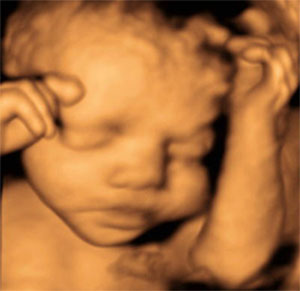

UCSF‘s ultrasound subspecialty utilizes state-of-the-art, high-resolution ultrasound machines equipped with 2D, 3D and 4D capability along with color and duplex doppler imaging to create real-time sonograms of patients.